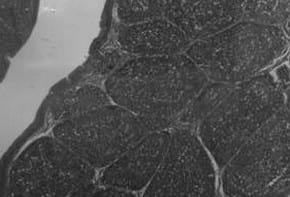

Figura 1: Micrografias de Bursas de Fabricio. 40x. Pollos de 42 días de edad. Grupo A (control) bursa normal, folículos linfoides homogéneos con distribución uniforme de la población linfocitaria. Grupo B (cepa suave), bursa similar a lo observado en el grupo control. Grupo C (cepa intermedia) bursa con aspecto completamente normal, similar a lo observado en los grupos A y B. Grupo D (cepa intermedia plus), se observan folículos linfoides con 1: depleción linfoide centro folicular, 2: persisten aún focos de necrosis, 3: intento de repoblación linfoide, 4: edema interfolicular.

En el estudio de reactividad de las bursa por histopatología (Cuadro 2) se observó que hubo diferencias significativas (P<0,05) a los 8 días post vacunación entre el grupo D (vacunado con la cepa intermedia plus) y el resto de los grupos. A los 16 días post vacunación, la mejor reactividad la presentó el grupo A (control) con diferencias significativas con los demás grupos de tratamiento, mientras que a los 22 días la reactividad fue igual para todos. A los 32 días post vacunación hubo diferencias significativas en el grupo D, presentando menor reactividad (Figura 1) con respecto a los demás grupos.

Los resultados de esta investigación nos indican que en el grupo A (control) y el grupo B (cepa suave) los cambios de maduración folicular son similares y obedecen al progreso orgánico e inmunológico del ave, evolucionando de acuerdo a la edad para la época de beneficio, concordando esto con la relación PB/PC. En el grupo C (cepa intermedia) la recuperación de la población linfocitaria en los folículos linfoides después del proceso de necrosis inicial es adecuada y acorde con la relación PB/PC.